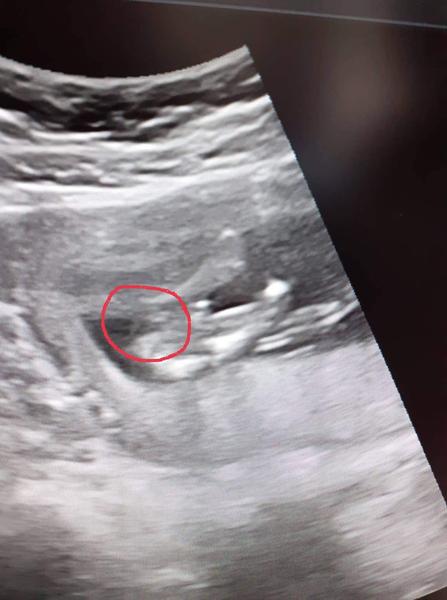

Ahoj maminky a budoucí maminky 😉 Prosím, poradila byste mi některá, co vidíte na fotce z ultrazvuku ve 20. týdnu za pohlaví? Určitě jste foteček viděly už mraky, proto vás žádám o radu...Nechci nikoho ovlivnit, proto svůj tip řeknu později 🙂 Děkuju moc!!!

@veru1999 jestli na té spodní fotečce je vidět pohlavní hrbolek a nepletu se,tak to spíše vypadá na chlapečka ♥

@charlotte28 nevim jestli se mi to zda ale dole vidím hrbolek. Vypadá to na kluka